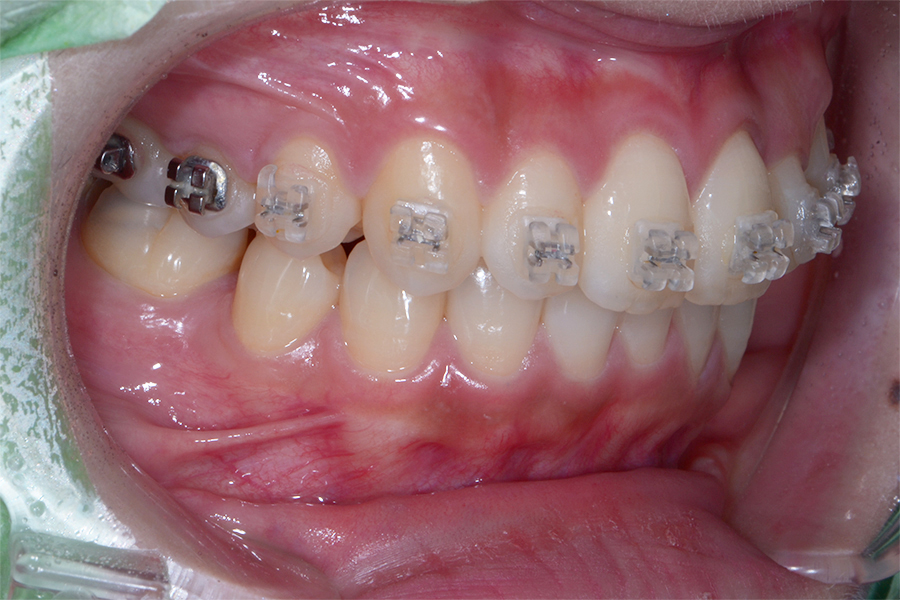

• 治療前

担当医 三留先生

主訴 引っ込んで捻じれてる歯を

綺麗にしたい

期間 治療期間8か月

治療内容 上顎ラビアル矯正(表側矯正)